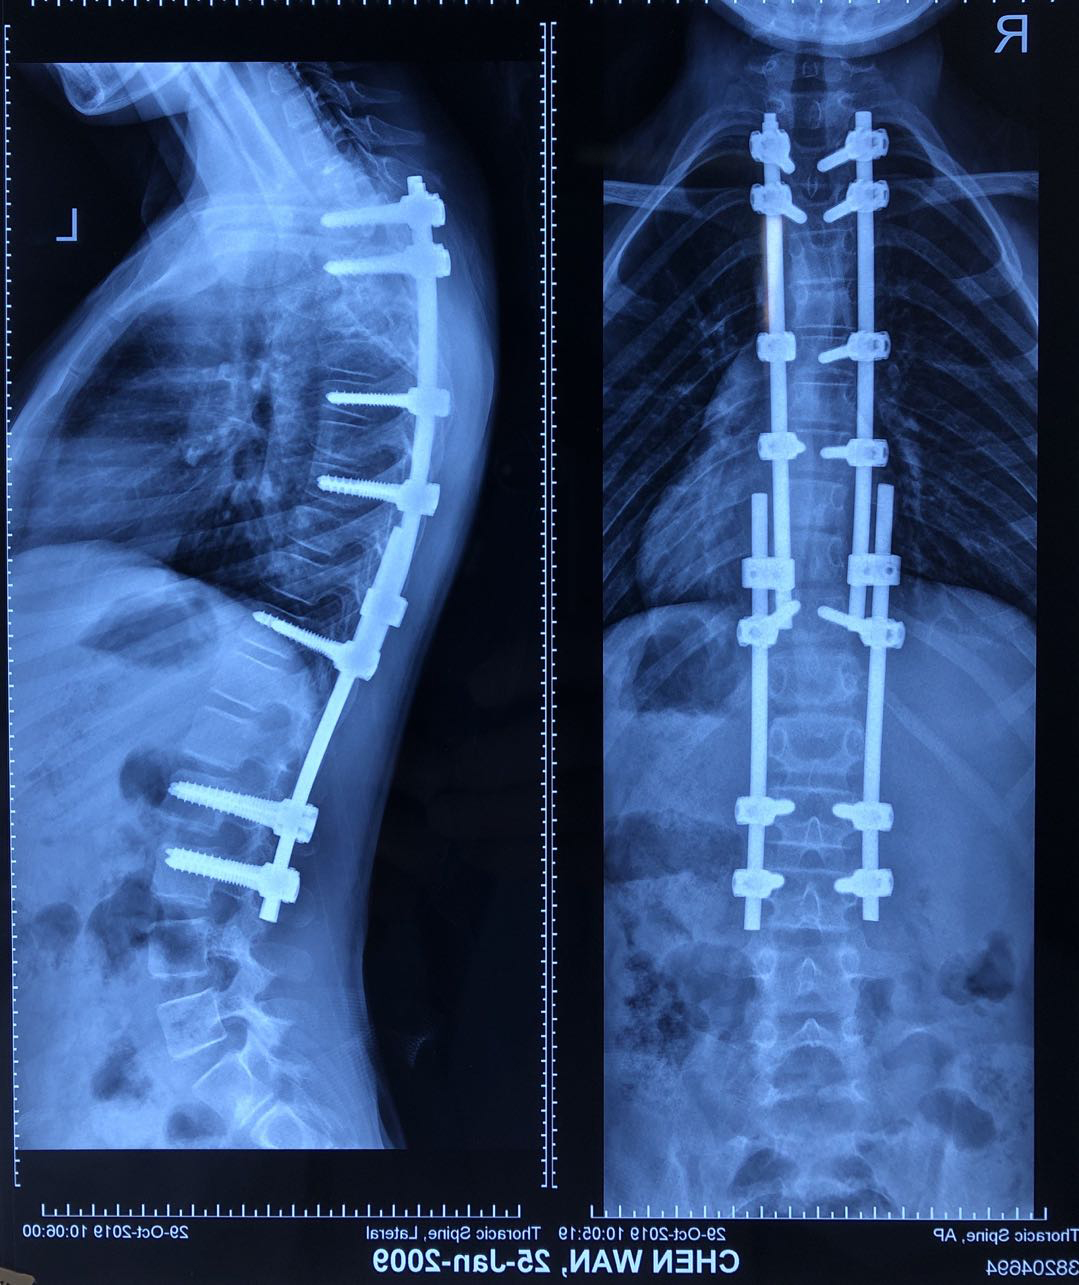

病例五:患者陈某,男性,10岁8月,云南省威信县人,因“发现胸背部畸形3年余”入院,诊断为:脊柱侧后凸畸形并功能障碍(休门氏病),行经后路胸椎SPO截骨矫形生长棒内固定术。

术前DR及CT

术后DR

术前术后站立位对比